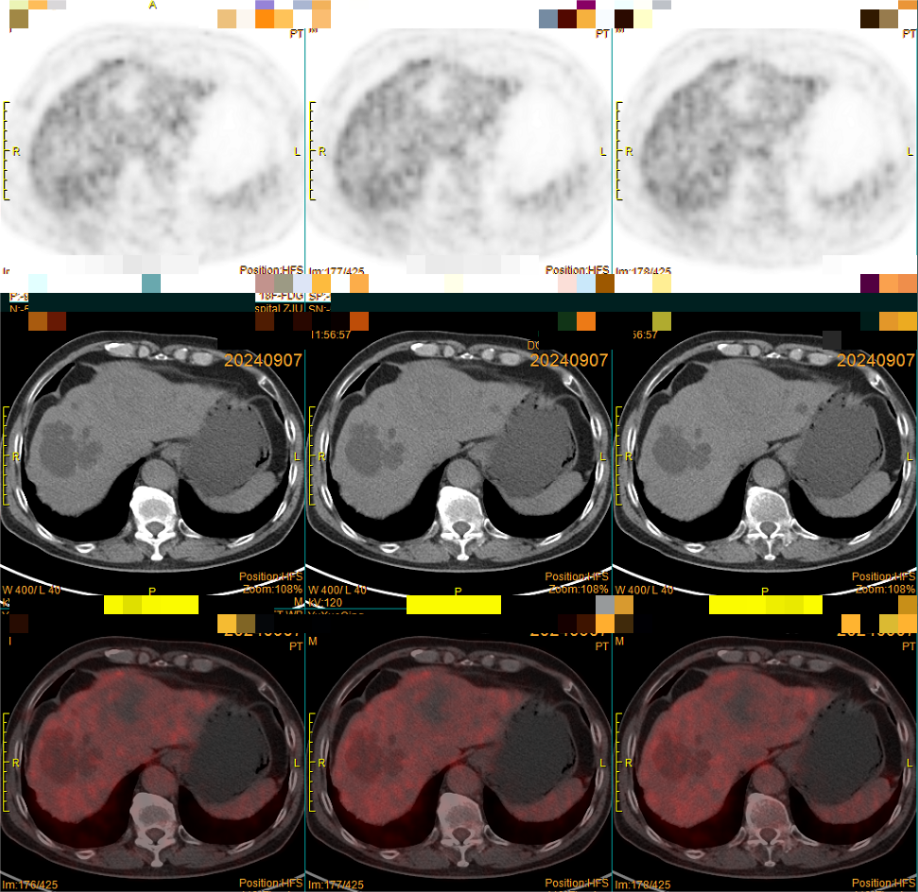

(图3)PET-CT提示:左肝低密度灶,18F-FDG摄取不明显(中央坏死区摄取低于正常肝组织)。